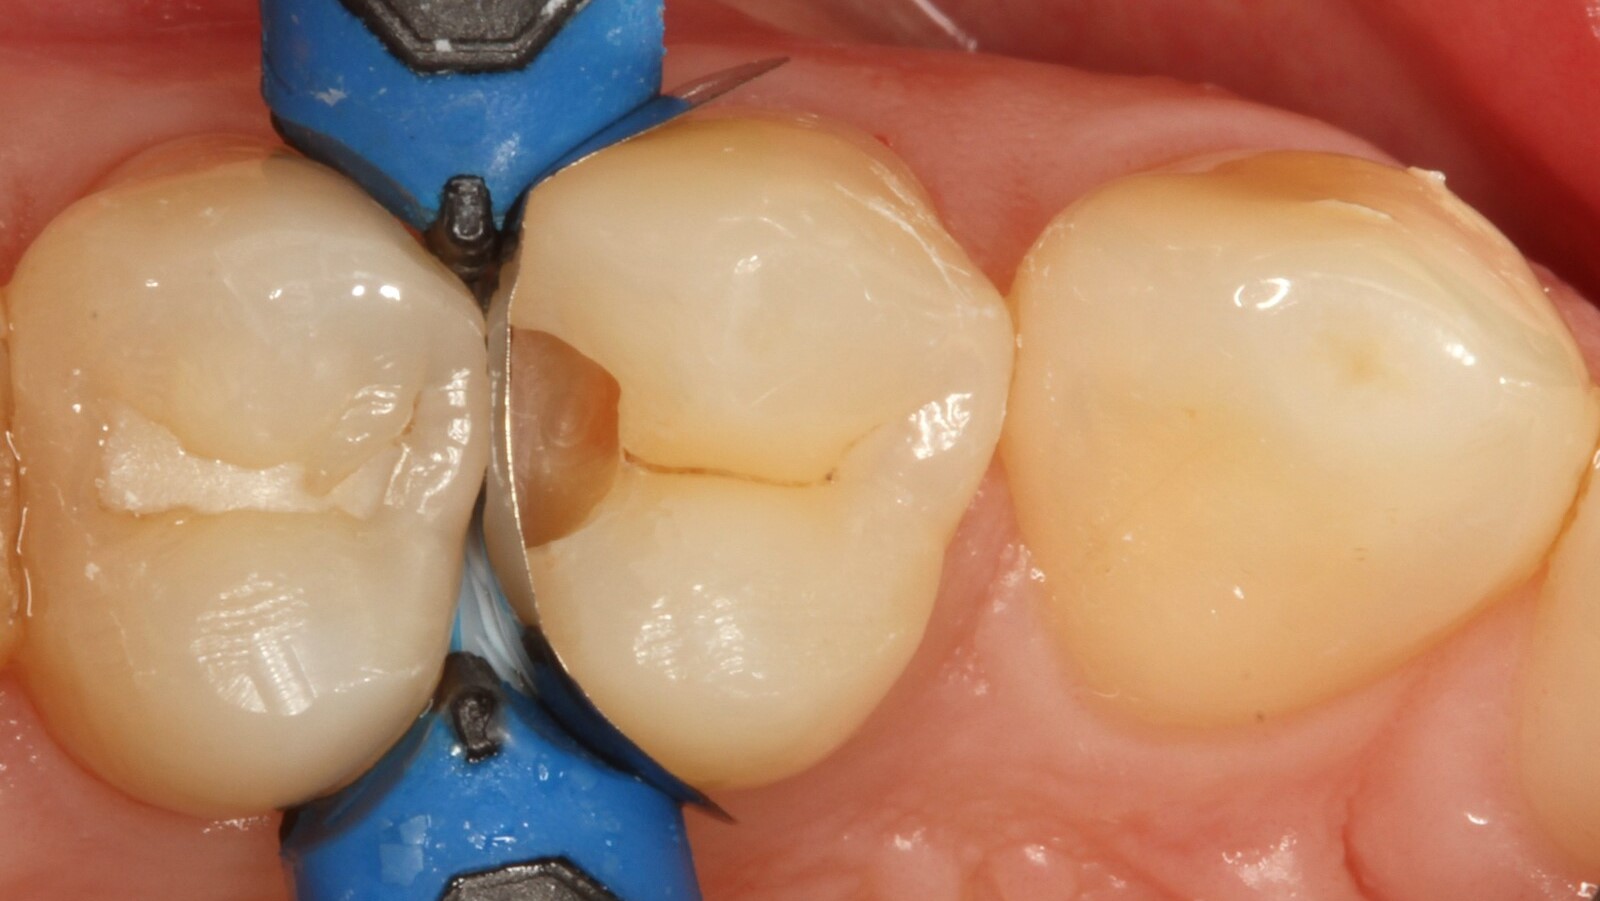

Professor Ernst first identified the hidden caries and opened the carious lesion to show the patient the problem (Fig. 1-2). He then excavated the caries, prepared the cavity and placed a sectional matrix (Fig. 3) before sealing the cavity with adhesive (Fig. 4). In a single step, he filled the cavity with Venus Bulk Flow ONE (Fig. 5). Once the restoration was completed, Prof. Ernst polished it (Fig. 6) and took a control radiograph, which also shows the excellent radiopacity of Venus Bulk Flow ONE (Fig. 7).